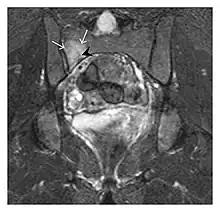

The sacrum is usually masked by overlapping bowel gas in conventional radiographs, and the subtle radiographic findings are usually nondiagnostic and even misleading. The characteristic "H" pattern has been correlated with biomechanical models of patient activities. The vertical parasagittal planes correspond to the region of maximal stress during walking, while the horizontal fracture develops later, secondary to the loss of lateral support by parasagittal fractures. MRI is the primary imaging technique in this case, with the most common MRI pattern showing bone marrow edema and a fracture line (Figure 12). Coronal views are quite contributive in sacral fractures, allowing the detection of the horizontal component, especially with fluid-sensitive sequences. Although the sacrum is the most commonly involved, pelvic insufficiency fractures are often multiple, and other typical locations should be mentioned.[1]

Proximal femoral fractures usually occur in osteoporotic patients, and their signs include subtle neck angulation, trabecular angulation, and subcapital impaction line. A frog-leg lateral view may be helpful if the greater trochanter is short enough. However, positioning can be difficult because of hip pain. In patients with strong suspicion of proximal femoral fracture and negative radiographs, MRI limited to coronal T1 W images and scintigraphy can be highly valuable (Figures 13 and 14). Such an option, with limited examination time, is cost-effective and allows reliable exclusion or confirmation of the diagnosis, preventing an unnecessary stay at the hospital or delayed treatment. Moreover, MRI helps to detect soft tissue abnormalities which are more frequently seen in femoral, acetabular, and pubic injuries than sacral lesions. Concomitant fractures are also frequently seen in typical pelvic sites.[1]

a

b

Figure 13: Partial osseous avulsion of the gluteal muscles at the greater trochanter in a 59-year-old man who presented with the right hip pain without a history of trauma. Lauenstein view and anteroposterior and radiographs (not shown) did not show an obvious fracture line or disruption of bony contours in the acetabulum or the right femoral neck. (a) Coronal T1-weighted MRI displays an incomplete fracture line extending partially from the greater trochanter (arrow). (b) Coronal short tau inversion recovery MRI shows heterogeneous hyperintensity in the same region (arrow) as well as hyperintensity within the gluteus medius and minimus muscles (arrowheads) consistent with tissue edema and hematoma.[1]

Figure 14: Subcapital insufficiency fracture in a 55-year-old man with a left hip pain without a history of trauma. Anteroposterior and Lauenstein view radiographs centered on the left hip do not show an obvious fracture line, but mild acetabular osteophytosis was noted consistent with hip osteoarthritis (not shown). (a) Coronal T1-weighted MRI shows a linear low-signal band through the femoral neck corresponding to a fracture line (arrowheads). (b) Bone scintigraphy shows focal uptake (arrow) corresponding to the fracture.[1]